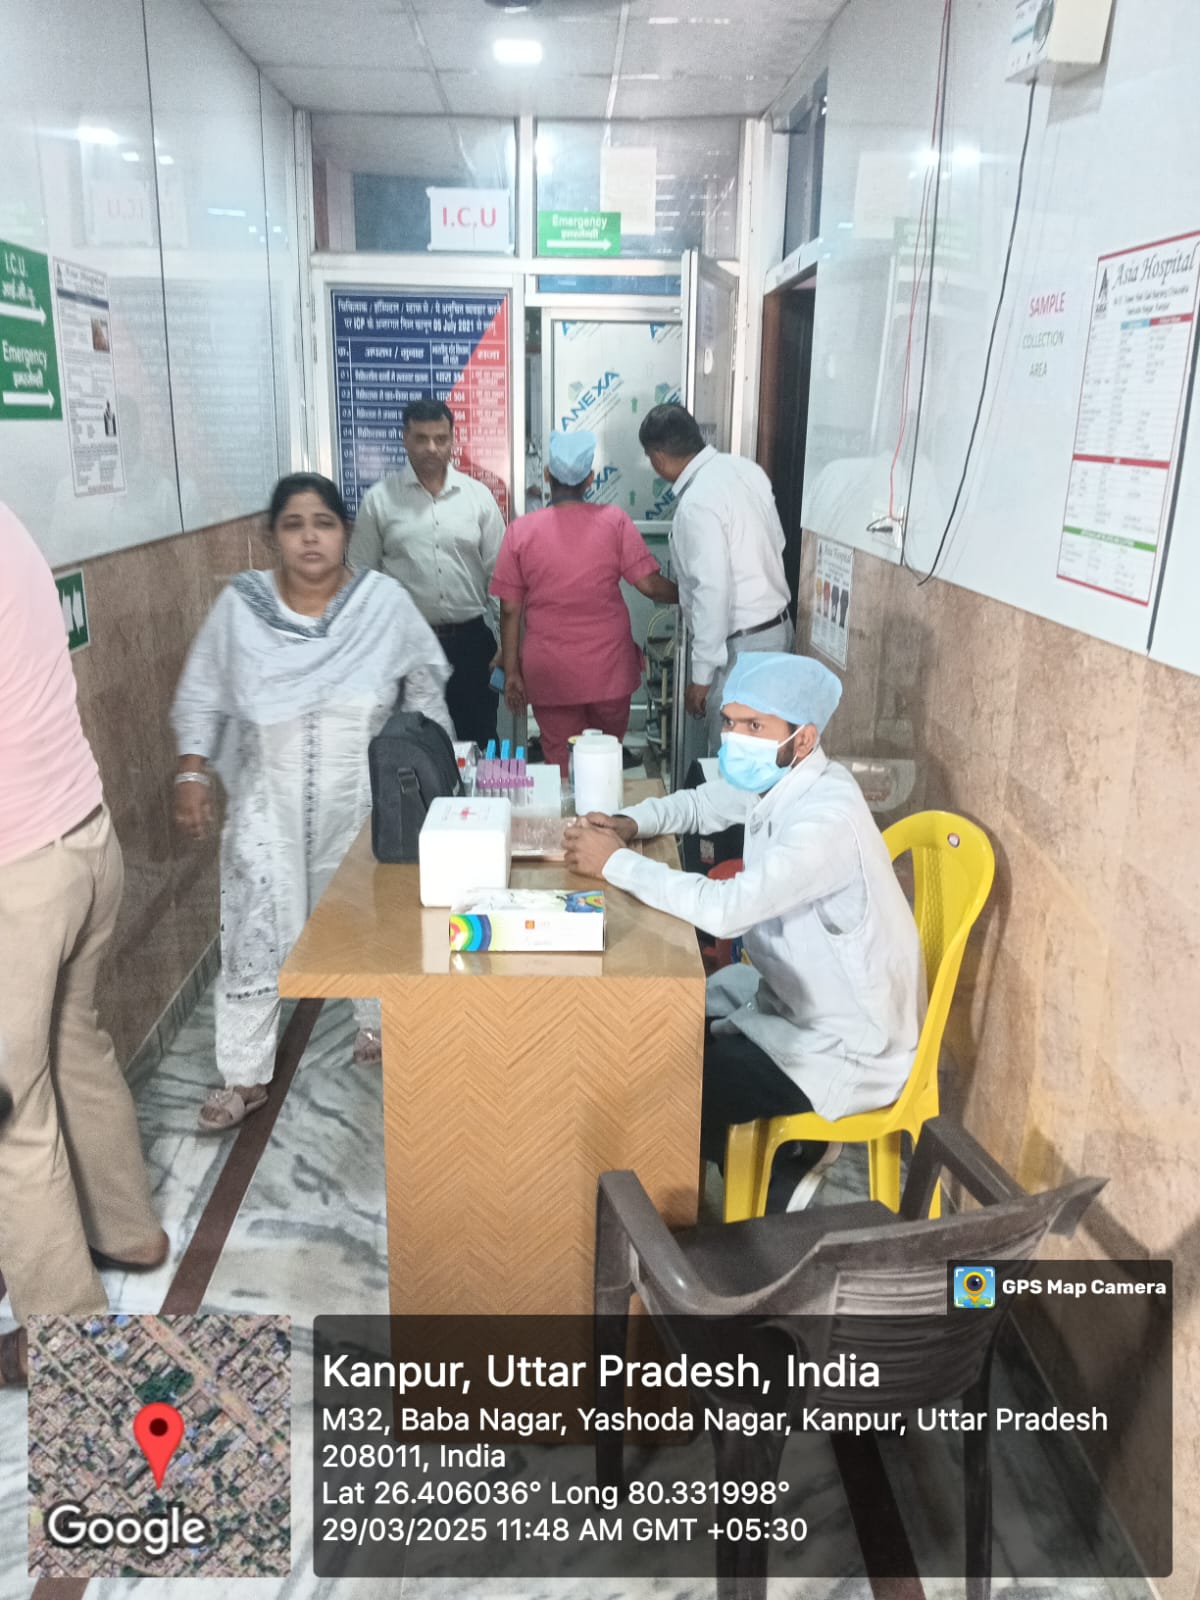

See Our Work!

Here’s a quick look at the beauty transformations that we have worked on. Whether it is a

temporary makeup or a complete makeover, you can trust us.